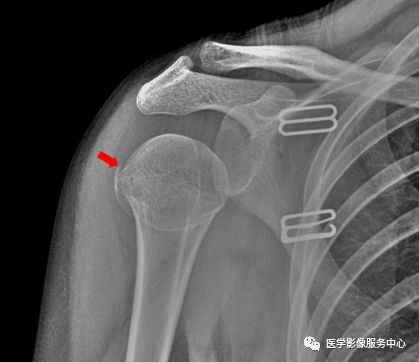

踝关节

图片

右侧外踝骨皮质连续中断,可见透亮骨折线影,可见软组织稍肿胀影。右踝关节骨折。

Warmreminder: 踝关节扭伤,许多大夫只做踝关节正侧位。有时踝关节正侧位不能看出有明显异常,而有局部软组织肿胀,活动受限时,根据我的经验,踝关节扭伤有时只做正侧位是有局限性的;小妙招足正位也是必不可少的。

此患者就是踝关节扭伤,踝关节正侧位未见异常,加拍足正位时发现外踝骨折。

所示右侧腓骨远端见斜行骨折线,骨折端对位对线尚可。右腓骨远端骨折。